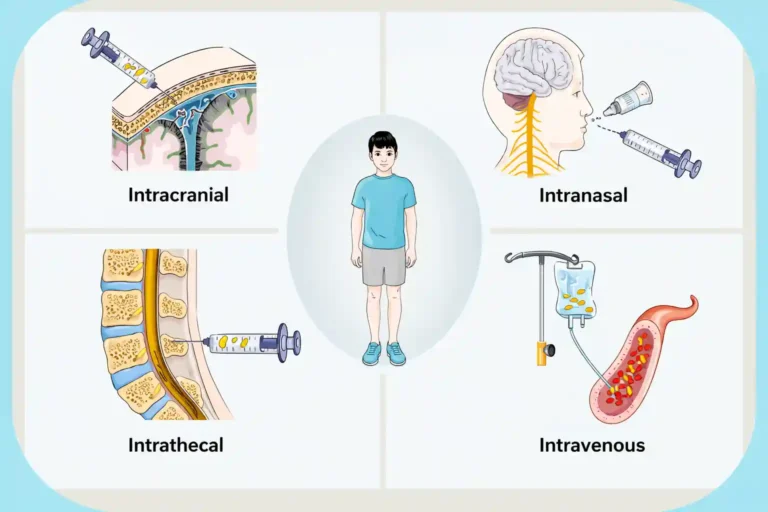

Procedure

- Detailed neurological evaluation

- Imaging review

- Medical clearance

- Targeted stem cell administration

- Physiotherapy and rehabilitation

- Long-term follow-up monitoring

Procedure

- Pediatric neurological evaluation

- Imaging confirmation

- Safety screening

- Controlled stem cell therapy

- Physiotherapy integration

- Developmental progress monitoring

Procedure

- Cognitive and neurological assessment

- Brain imaging review

- Medical clearance

- Targeted stem cell administration

- Cognitive therapy support

- Regular monitoring and reassessment

Procedure

- Neurological assessment

- Imaging review

- Medical clearance

- Controlled stem cell therapy

- Physiotherapy and motor training

- Ongoing monitoring